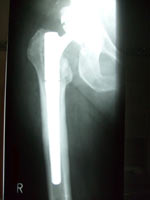

• Durch Knochenerweichung (Osteoporose), Entzündung, Knochenbruch oder andere Ursachen kann eine Prothesenlockerung auftreten. Dann werden einzelne Komponenten oder die ganze Prothese gewechselt. Zum Einsatz kommen Standard- oder Spezialprothesen. Beim Protheseninfekt kann auch eine Interimsprothese aus Antibiotika-beladenem Knochenzement für einige Wochen eingesetzt werden.

Kurzschaftprothese Kurzschaftprothese Sonderprothese Sonderprothese